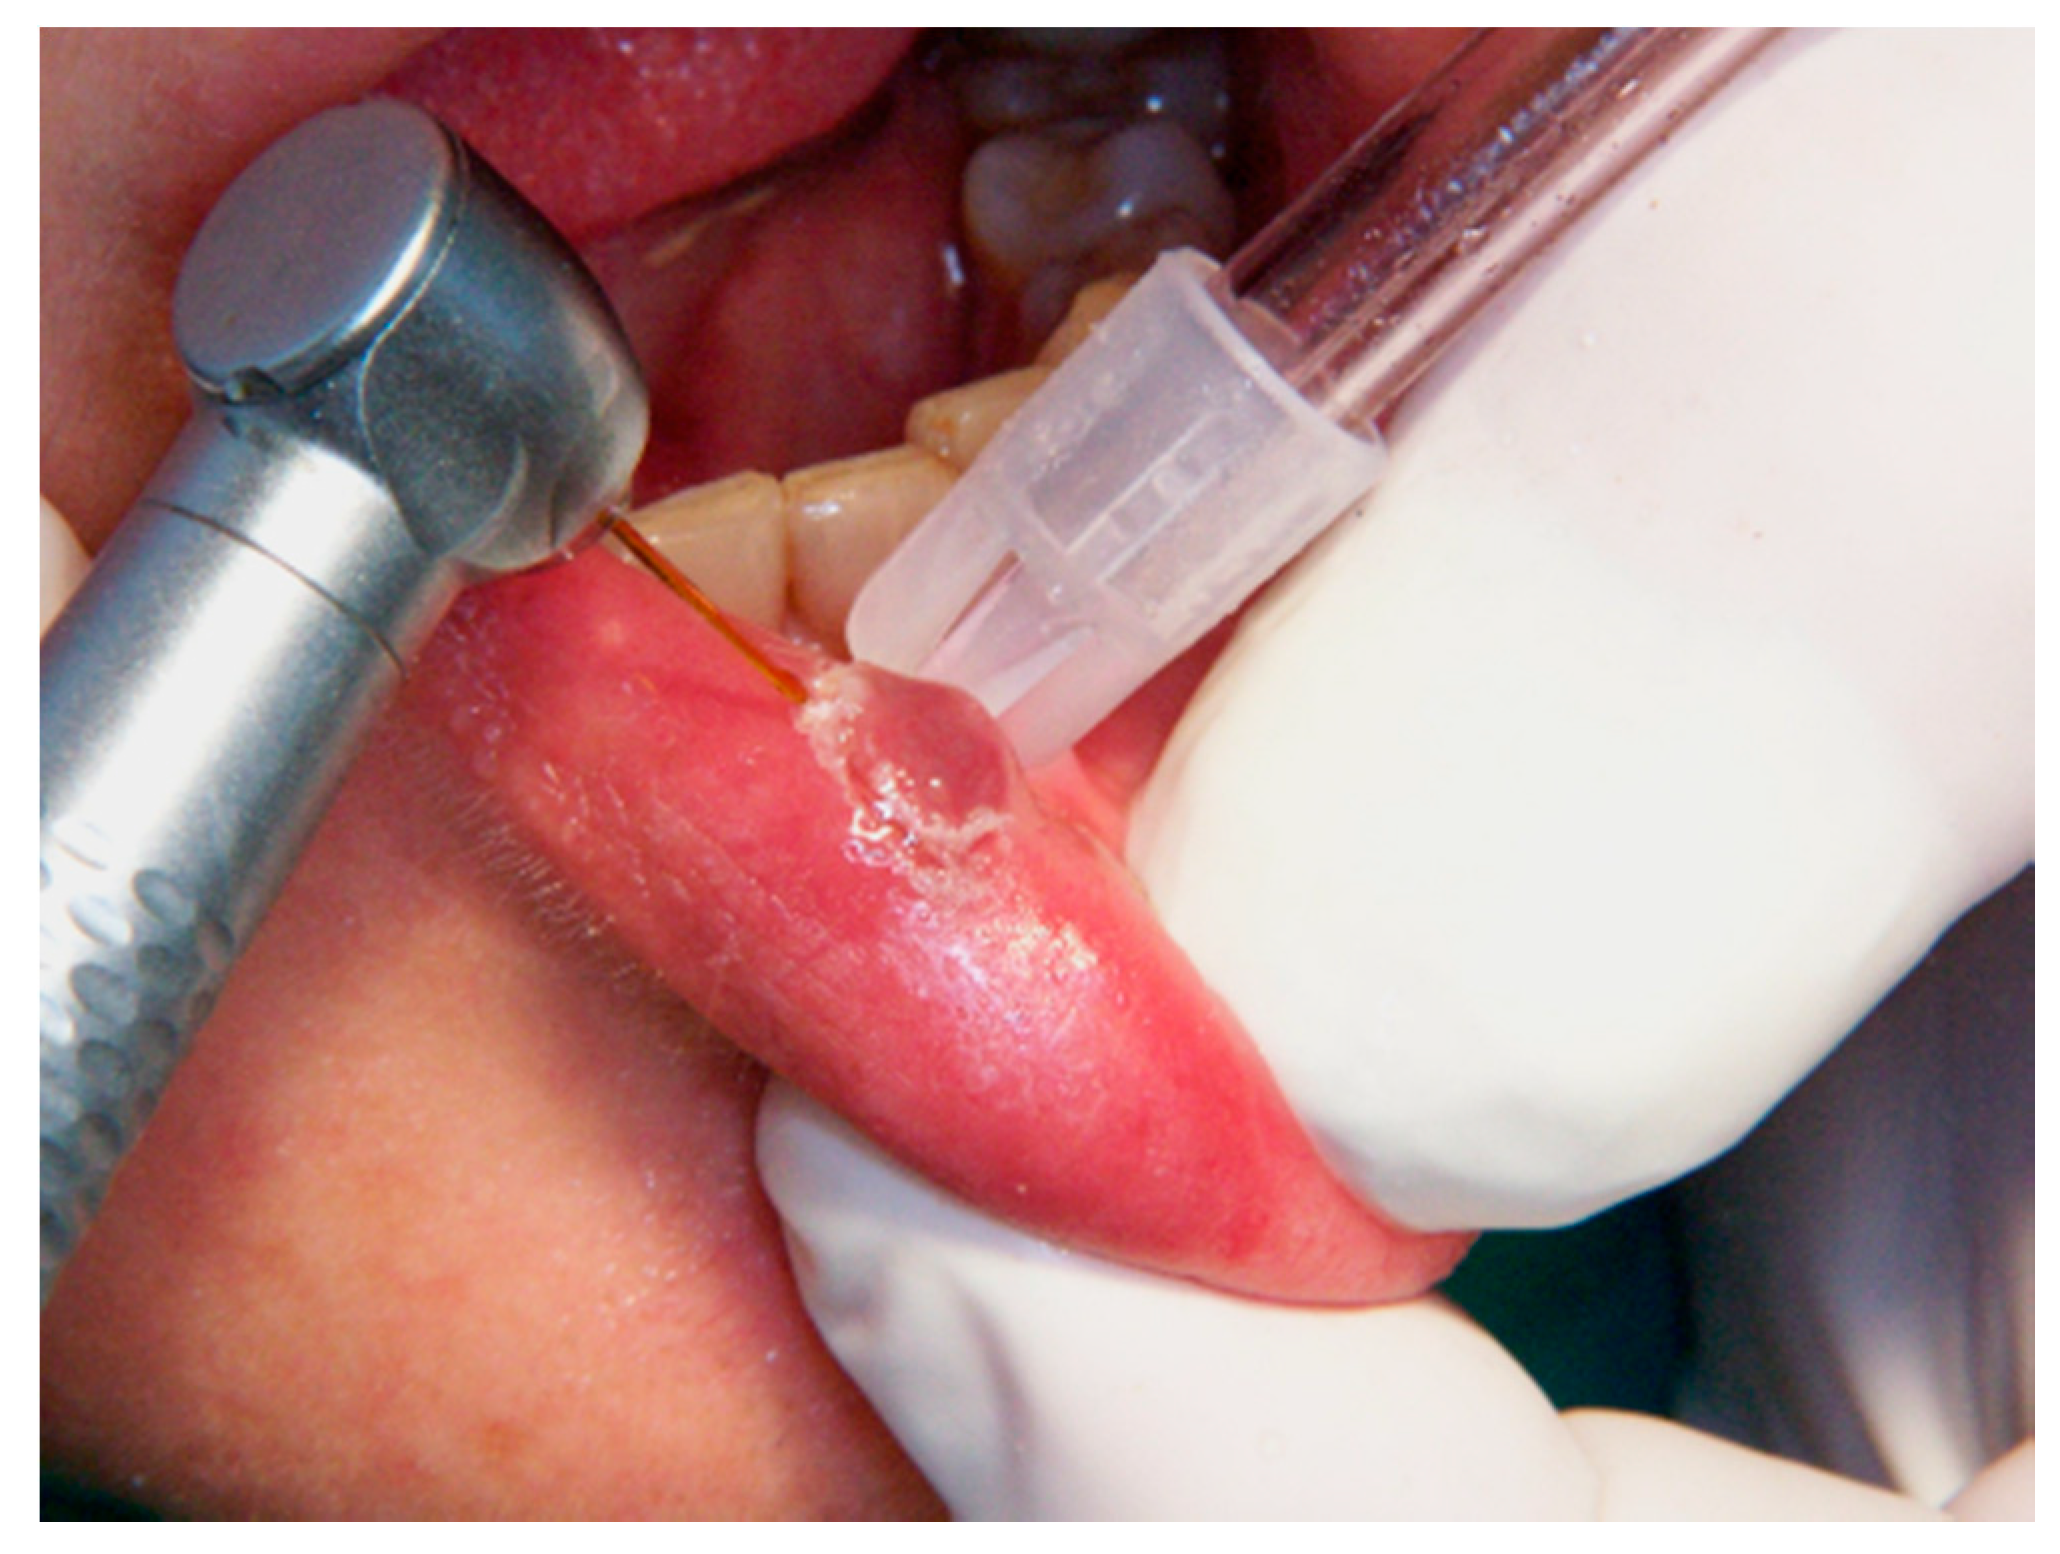

Figure 2.

The lesion’s resection limit is indicated by the Er,Cr:YSGG laser around the surgical site.

2.3.1. Er,Cr:YSGG Laser

An Er,Cr:YSGG laser with a wavelength of 2790 nm (Waterlase, Biolase Inc., Foothill Ranch, CA, USA) was used. After the injection of local anesthesia, the excision areal limit was delimited by the laser beam without air–water spray with an output power of 0.25 W and 20 Hz (Figure 1, Figure 2 and Figure 3). An excision was made for all lesions with an output power of 1.5 to 2 W (27 J/cm2), a fiber diameter of 600 μm, and pulsed mode (20 Hz, 60 μs). In addition, a defocused (noncontact) mode without air–water spray was used for the coagulation of the bottom of the wound at the end of the excision to ensure a primary coagulation. The wound was left to heal in the second intention, and no sutures were made.